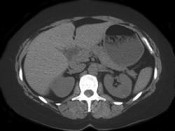

- 单项选择题女性,最近感腰部胀痛, 体检发现B超右肾正常,左肾有一囊肿, 双肾体积不增大,尿常规、肾功能正常, 无家族病史,CT表现如图所示, 最可能考虑为 ( )